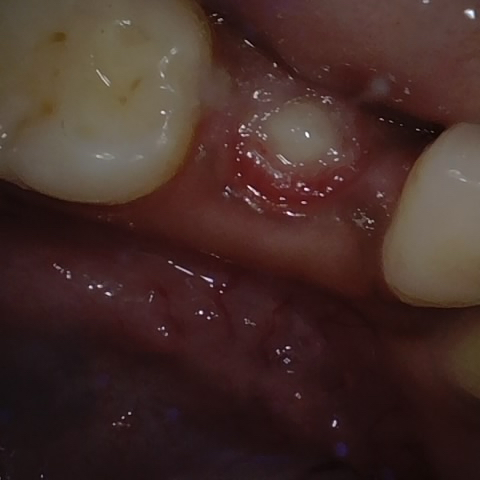

Annotated as "Good"